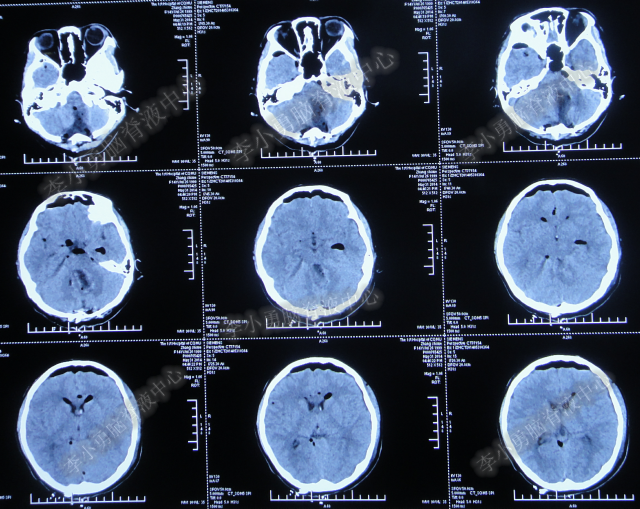

2014年8月31日住入李小勇脑脊液中心,入院时:卧床,表情淡漠,神志嗜睡;体温高37.9°C;头颅枕后正中手术瘢痕,结痂尚未脱落;左枕侧脑室外引流固定在位,尚通畅,可见淡红色浑浊脑脊液引出;颈抵抗,双肺呼吸音粗(图-27);头部CT检查示(小脑肿瘤术后颅内感染病例)脑室系统粘连严重伴双侧颞角脑室扩张明显,双侧侧脑室见引流管影,脑内见多发斑片低密度,中线结构无移位,颅骨术后改变(图-28)。

图-27:2014年8月31日入院时

图-28:2014年8月31日头部CT

入院第4天即2014年9月3日,左枕脑室外引流管引流脑脊液量不多,晨起4:00左右出现血压升高伴瞳孔扩大,4.5:2.0;多参数生理:心率102次/分,呼吸11次/分,血压141/96mmHg,血氧饱和度98%;急行头部CT检查示双侧侧脑室扩大,颞角扩张显著,双侧侧脑室见引流管影,位置变化不大,脑内见多发斑片低密度(图-29)。

图-29:2014年9月3日4点50分头部CT